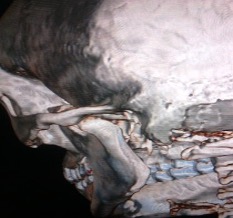

Case 2: A 22-year male patient reported to the department of dentistry after a road traffic accident. There was swelling in the left preauricular region with a history of ear bleed. Painful movements of the mandible were observed without any restrictions in mouth opening. Condyle was present in the glenoid fossa, and movements were perceptible bilaterally. The O.P.G revealed no fracture in either condyle, but the C.T. showed a sagittal fracture of the left condylar head and a medial displacement of the medial fragment. A soft diet and limited mouth opening were advised for two weeks.

Figure 4. Case 2: 3D CT showing vertical fracture of left condyle of mandible.